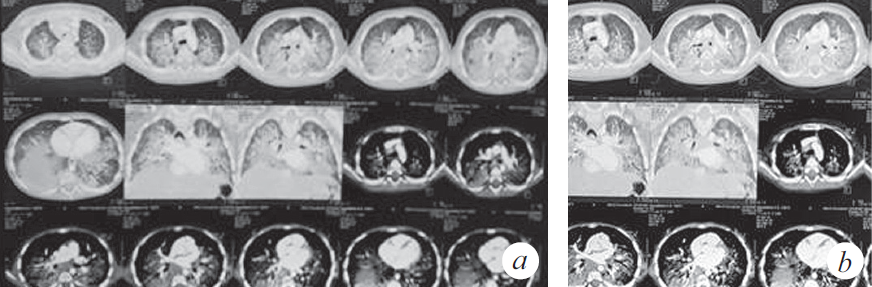

Из анамнеза заболевания известно, что 01.11.2018 ребенок по неосторожности родителей принял внутрь парафиновое масло. Мама стимулировала рвоту, после чего ребенок стал подкашливать. Бригадой скорой медицинской помощи девочка доставлена в стационар по месту жительства с диагнозом: «Острая респираторная вирусная инфекция, ларинготрахеит». О факте случайного приема парафинового масла и стимуляции рвоты мать не сообщила. Первые три дня пациентка находилась в стационаре (детская клиническая больница № 1) и, учитывая улучшение, была выписана под наблюдение участкового врача. На одиннадцатый день заболевания девочка с симптомами внебольничной двусторонней пневмонии была госпитализирована в стационар центральной клинической больницы СО РАН, с дальнейшим переводом в инфекционную больницу. По результатам компьютерной томографии (КТ) органов грудной клетки констатированы признаки диффузного интерстициального заболевания легких (рис. 1). На этом основании заподозрено аспирационное поражение паренхимы легких, вероятность которого подтвердила мать при дополнительном сборе анамнеза.

Рис. 1. Компьютерная томограмма органов грудной клетки (через 3 нед. от дебюта заболевания) (a). Признаки диффузного интерстициального заболевания легких, вероятно, двусторонняя липоидная пневмония, дифференциальный диагноз с альвеолярным протеинозом (b)

Fig. 1. CT scan of the chest (3 weeks after the onset of the disease) (a). Signs of diffuse interstitial lung disease, probably bilateral lipoid pneumonia, differential diagnosis with alveolar proteinosis (b)